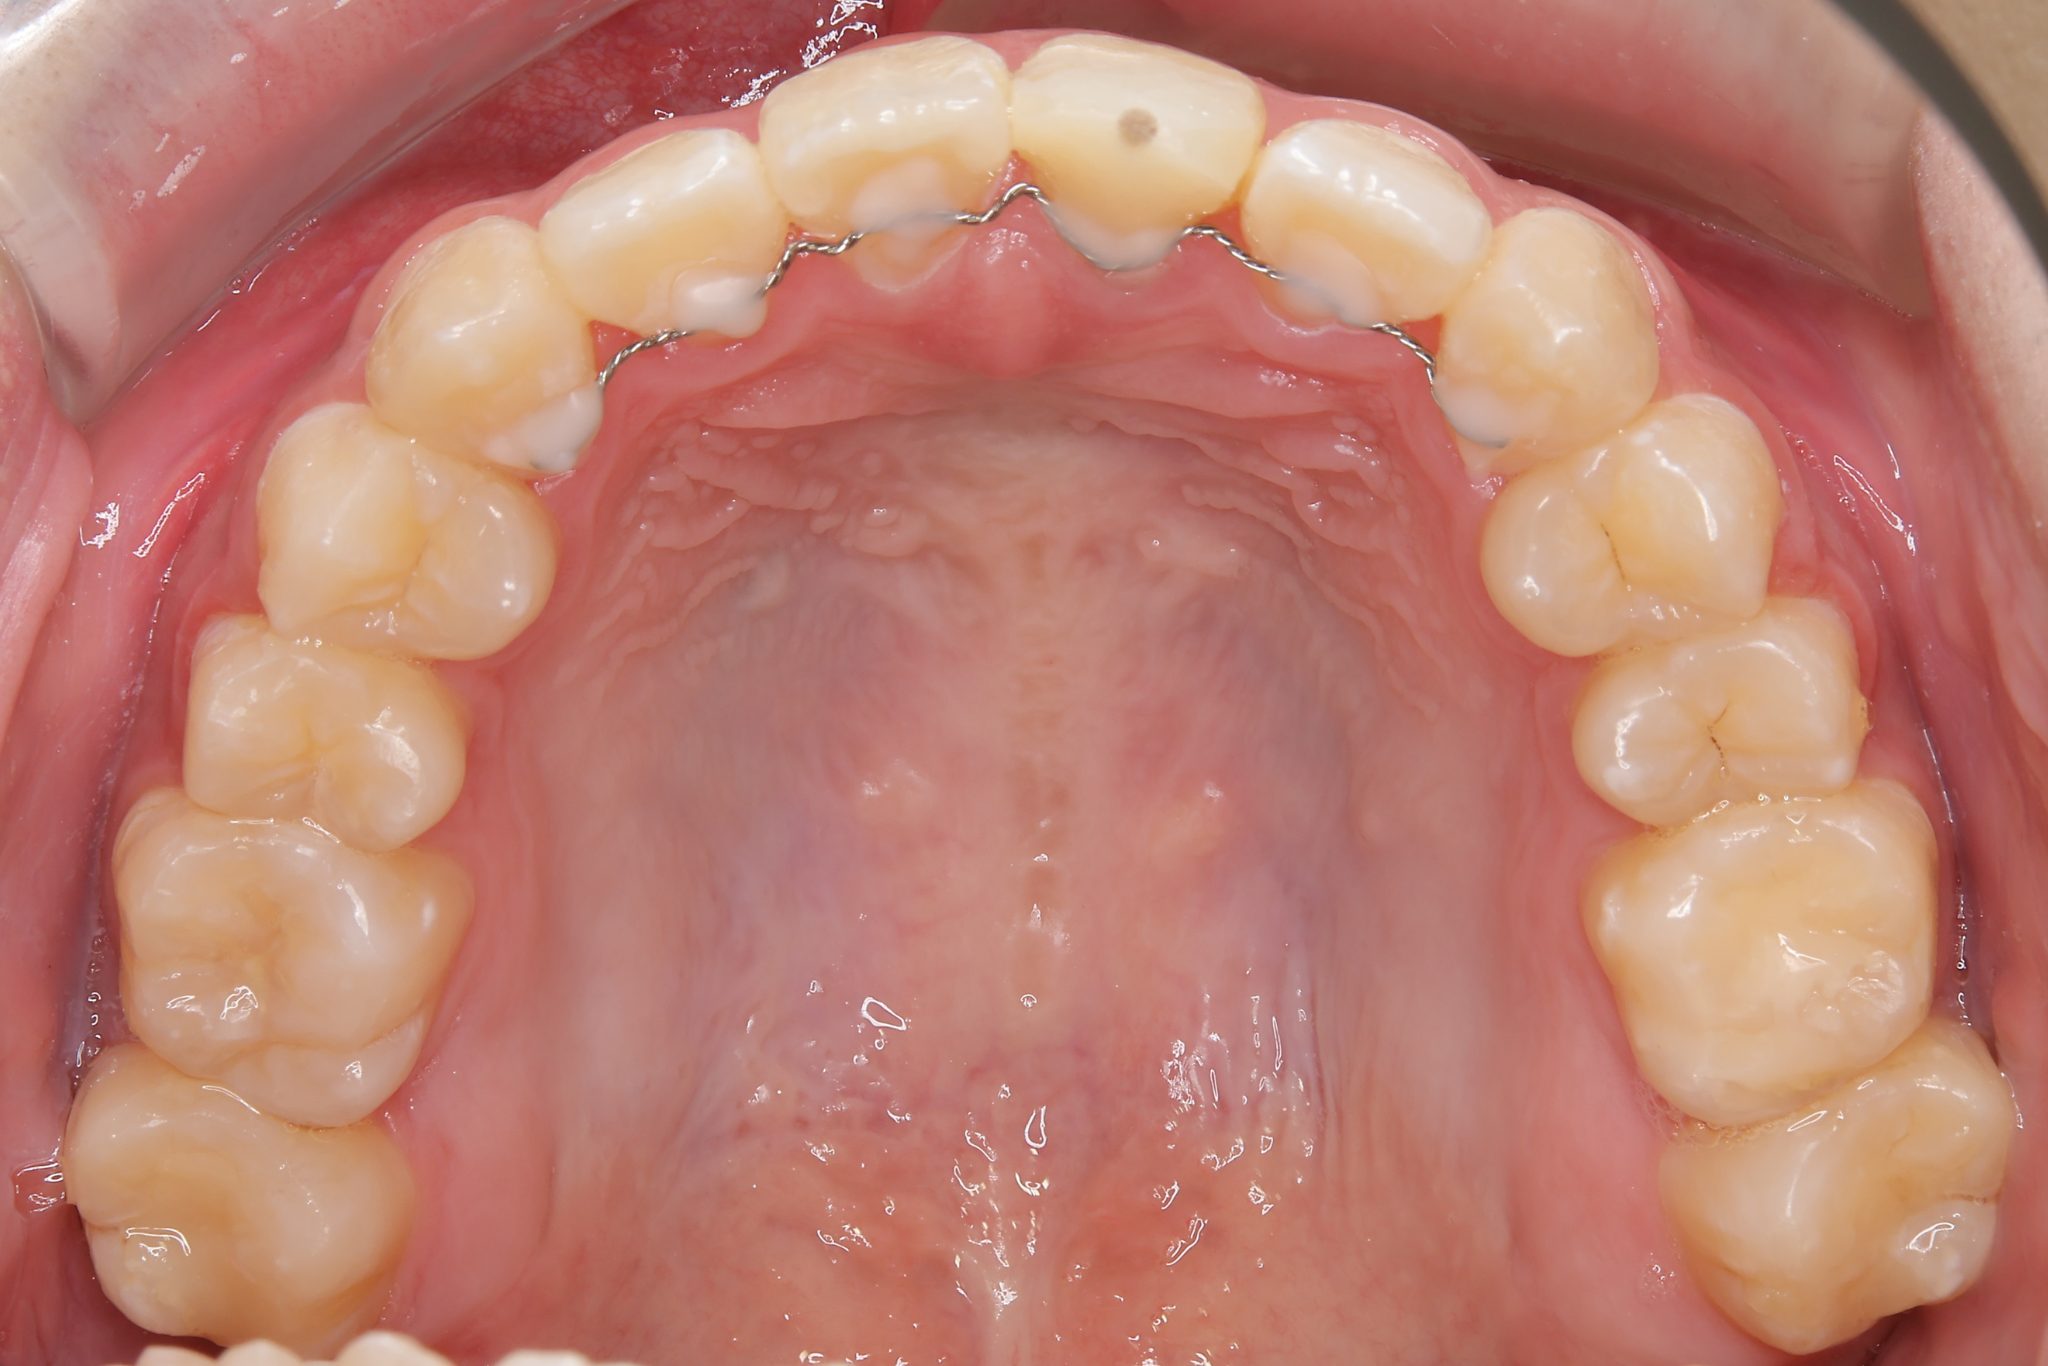

ビフォー

主訴 前歯が少し前に出ている|鼻づまり

施術内容 MSEと下顎リンガルアーチを用いて上下顎骨を拡大した。

その後をマルチブラケット装置を用いて非抜歯で歯牙を配列し、良好な咬合を獲得した。

治癒期間 1年6か月間